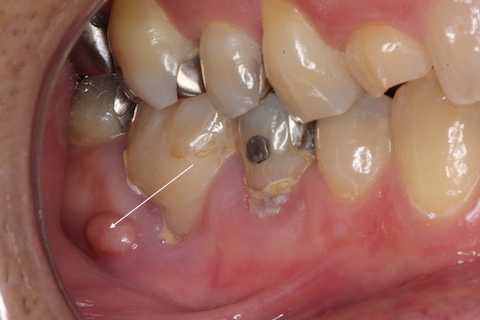

残根上のCR8 2025.10.28